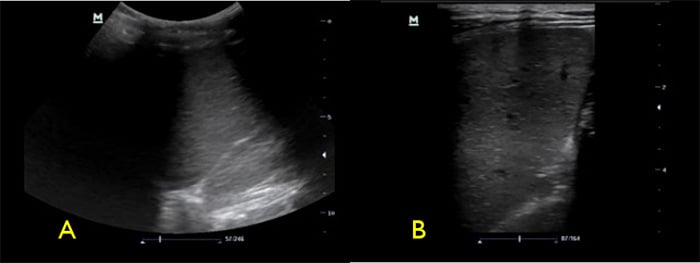

- Fan the transducer through the spleen to evaluate for focal splenic lesions.

- If no lesions are noted, switch to the high frequency linear transducer to evaluate the spleen for small focal hypoechoic lesions. (Video 5)

Video 5. Normal spleen with linear probe

Figure 4. Spleen with low frequency (A) vs high frequency (B) transducers